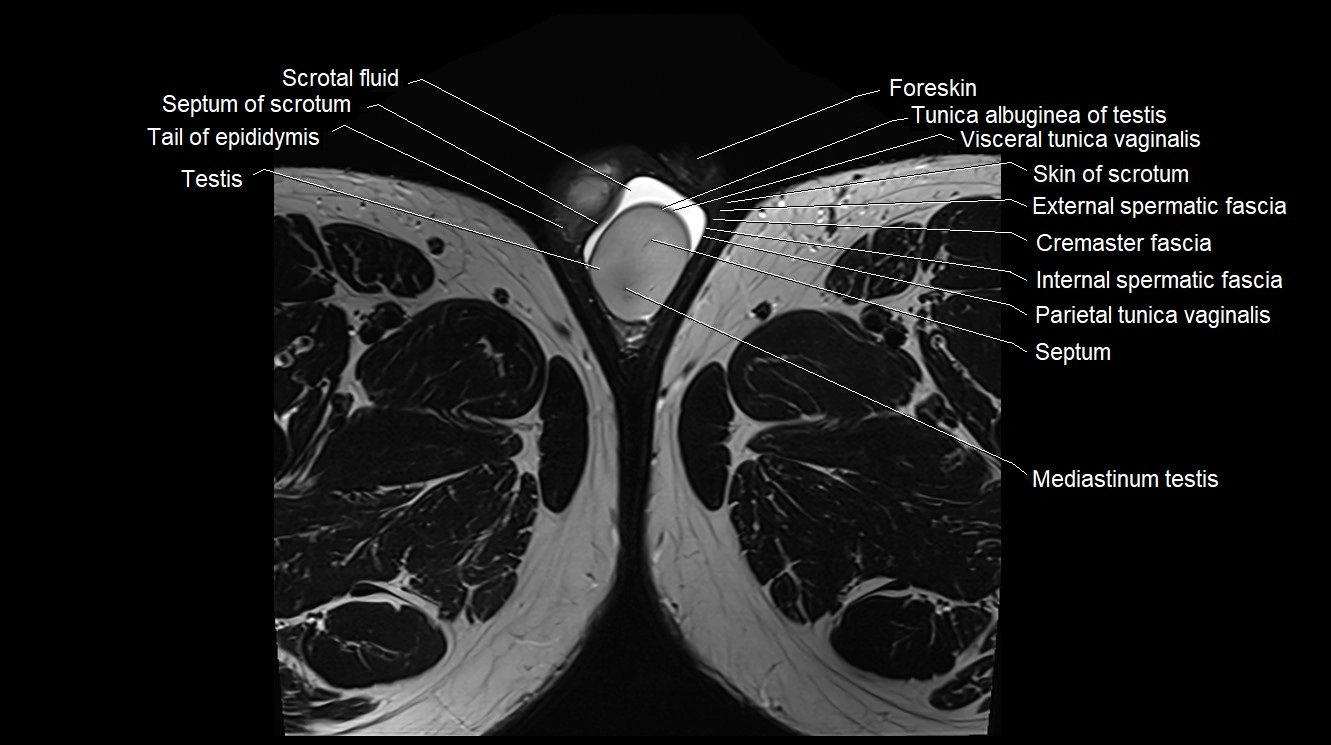

- External spermatic fascia

- Foreskin

- Mediastinum testis

- Membranous urethra

- Parietal tunica vaginalis

- Scrotal fluid

- Septum of scrotum

- Septum of testis

- Skin of scrotum

- Tail of epididymis

- Testis

- Tunica albuginea of testis

- Visceral tunica vaginalis